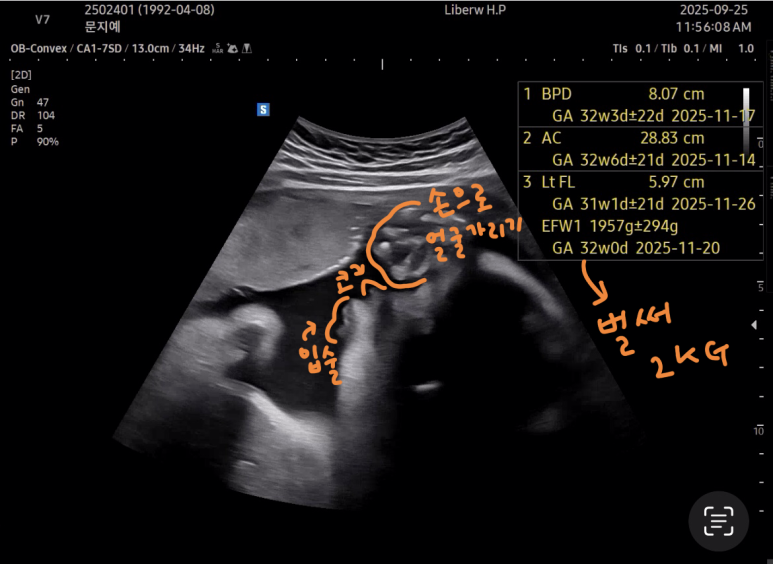

오랜만에 만난 사탕이는

역시나 손으로 얼굴을 가리고 있었다.

다행히도 머리가 밑으로 잘 가있었고,

갈비뼈 쪽이 엉덩이

배 오른쪽이 다리라고 하셨다.

어쩐지.. 갈비뼈가 많이 아프더라니 ~~

사탕이가 2kg 다되가서 그런가부다